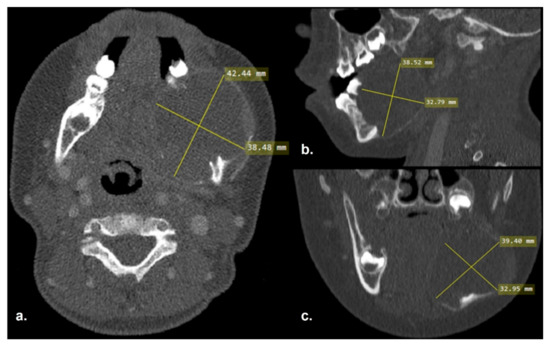

2.1. Clinical and Preoperative Radiological Presentation